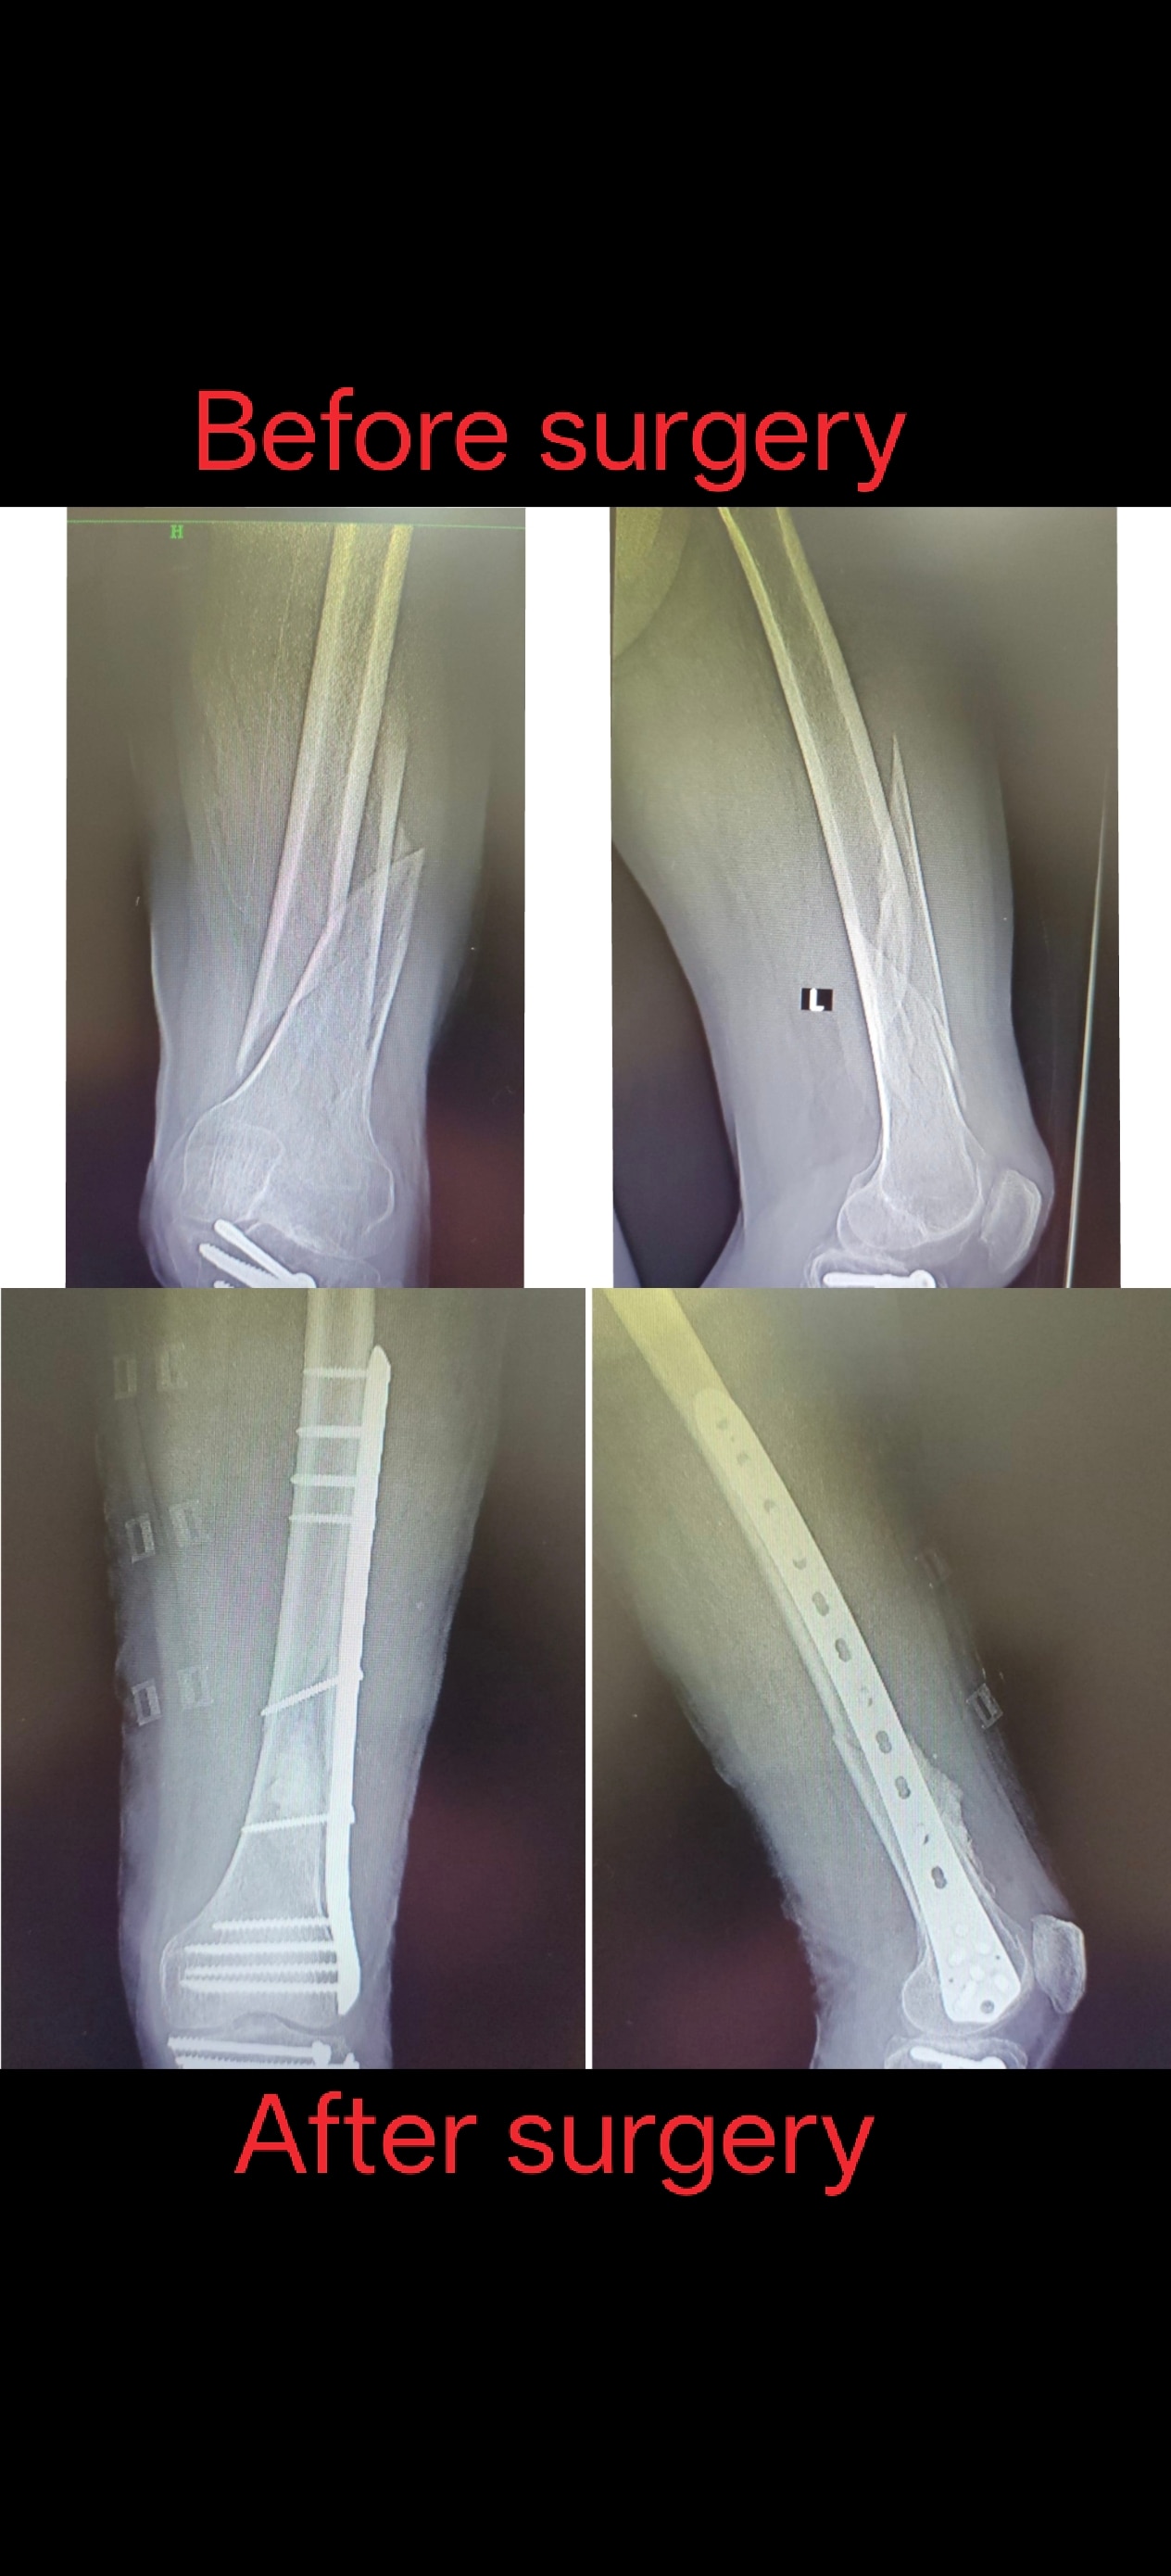

Welcome to the world of orthopedic excellence, where your health and well-being are our utmost priorities. Dr. Chetan Singh , an accomplished orthopedic surgeon, has been a dedicated practitioner in the vibrant city of Bhopal for the past 8 years. His unwavering commitment to providing exceptional orthopedic care has earned him a reputation as a trusted healthcare professional in the region. Meet Dr. Chetan Singh is a highly skilled orthopedic surgeon who has dedicated his career to improving the lives of patients suffering from orthopedic conditions. His educational journey began with the completion of an MBBS degree from Devi Ahilya Vishwa Vidyalaya, Indore, M.P. in 2015, where he laid the strong foundation for his medical expertise. Driven by his passion for orthopedics and a desire to offer the best care possible, Dr.Chetan Singh continued his educational journey. In 2019, he successfully achieved a Master of Surgery (MS) in Orthopedics from Madhya Pradesh Medical Science University, Jabalpur. This rigorous training equipped him with the knowledge, skills, and advanced techniques necessary to diagnose, treat, and manage a wide spectrum of orthopedic conditions.